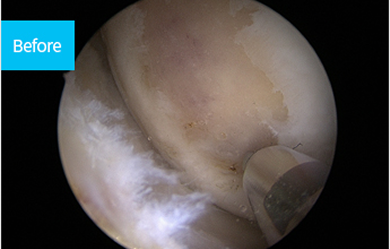

연골판 파열 치료방법

봉합이미지

1 ) 봉합술

일반적으로 관절경을 이용하여 반월연골판을 봉합합니다. 봉합하는 방법에는 여러 가지가 있습니다.

첫 번째 방법은, 관절경 시야에서 파열된 부위를 확인한 후 봉합 기구를 이용하여 관절 내부에서 시작해

관절 외부로 실을 뽑아내어 관절막에 매듭을 만드는 방식입니다. 두 번째 방법은, 관절 외부에서 유도관을 이용하여

파열 부위 및 반월연골판을 통과시킨 후 봉합사를 관절 외부로 빼내어 관절막에 매듭을 만드는 방식입니다.

바른마디병원 반월연골판 봉합술은 파열의 위치와 크기에 따라 적절한 방법을 선택합니다